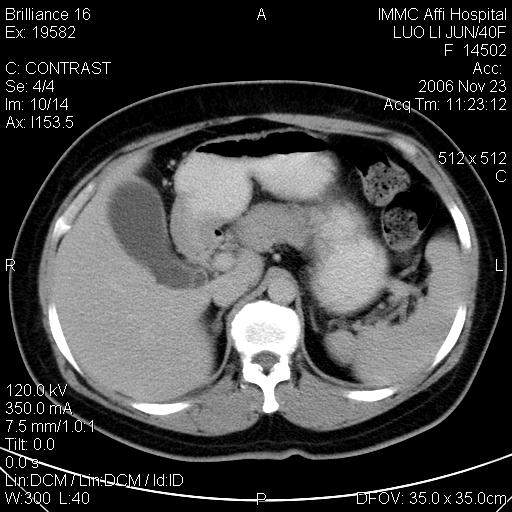

标题: CT5664:我也发一个肝脏的片子大家看看

速升速降,典型肝癌.

支持-----考虑肝癌----[-从片上看增强早期应该是动脉晚期即门脉早期]

是啊,典型的早出早归!

快进快出典型肝癌.

很好的片子,可惜增强做的比较失败,a期时间没有把我好,实际到了静脉早期了,否则会更典型。

最终考虑是肝腺瘤